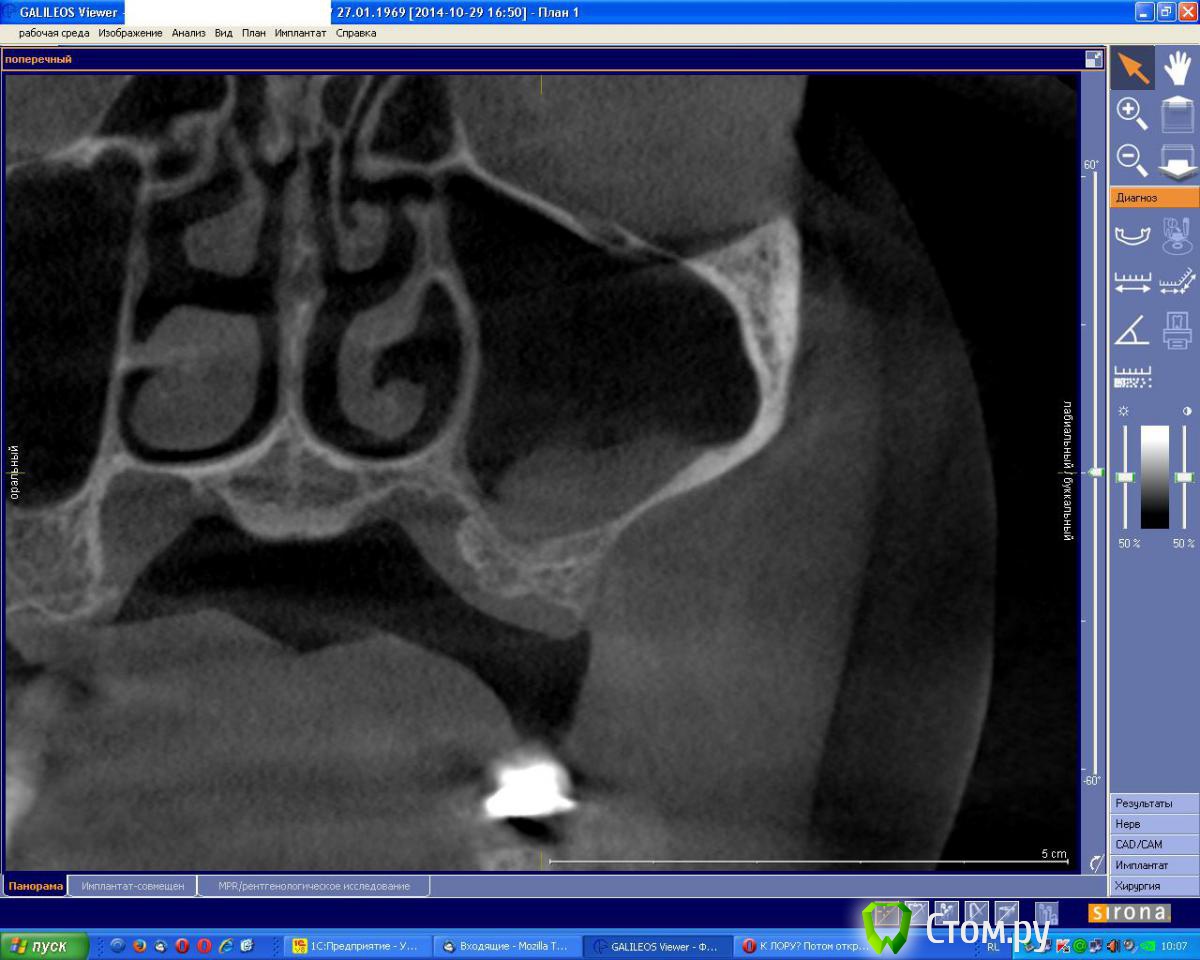

an_ver Опубликовано 1 ноября, 2014 Поделиться Опубликовано 1 ноября, 2014 Вот такой мешок увидел у пациентки.Вопрос: отправить к Лору а потом повторно КТ и открытый? Ссылка на комментарий

vesvova Опубликовано 1 ноября, 2014 Поделиться Опубликовано 1 ноября, 2014 Можно и без лора....Сразу на открытый.Но для точности, во фронтальной проекции посмотреть соустье.... Ссылка на комментарий

an_ver Опубликовано 1 ноября, 2014 Автор Поделиться Опубликовано 1 ноября, 2014 Открыто 1 Ссылка на комментарий

red_butler Опубликовано 1 ноября, 2014 Поделиться Опубликовано 1 ноября, 2014 +1 - ЛОР не нужен 4 Ссылка на комментарий

vesvova Опубликовано 1 ноября, 2014 Поделиться Опубликовано 1 ноября, 2014 Думаю,спокойно можете идти на синус Ссылка на комментарий

St_Klaus Опубликовано 1 ноября, 2014 Поделиться Опубликовано 1 ноября, 2014 Наверно, просто сопли в небольшом количестве. +1: без ЛОРа. Ссылка на комментарий

kriokov Опубликовано 2 ноября, 2014 Поделиться Опубликовано 2 ноября, 2014 an_verфронтальный срез классный залили, все что надо видно Ссылка на комментарий